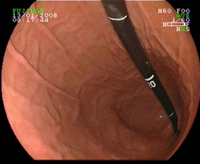

Clip ouvert en bout d'endoscope